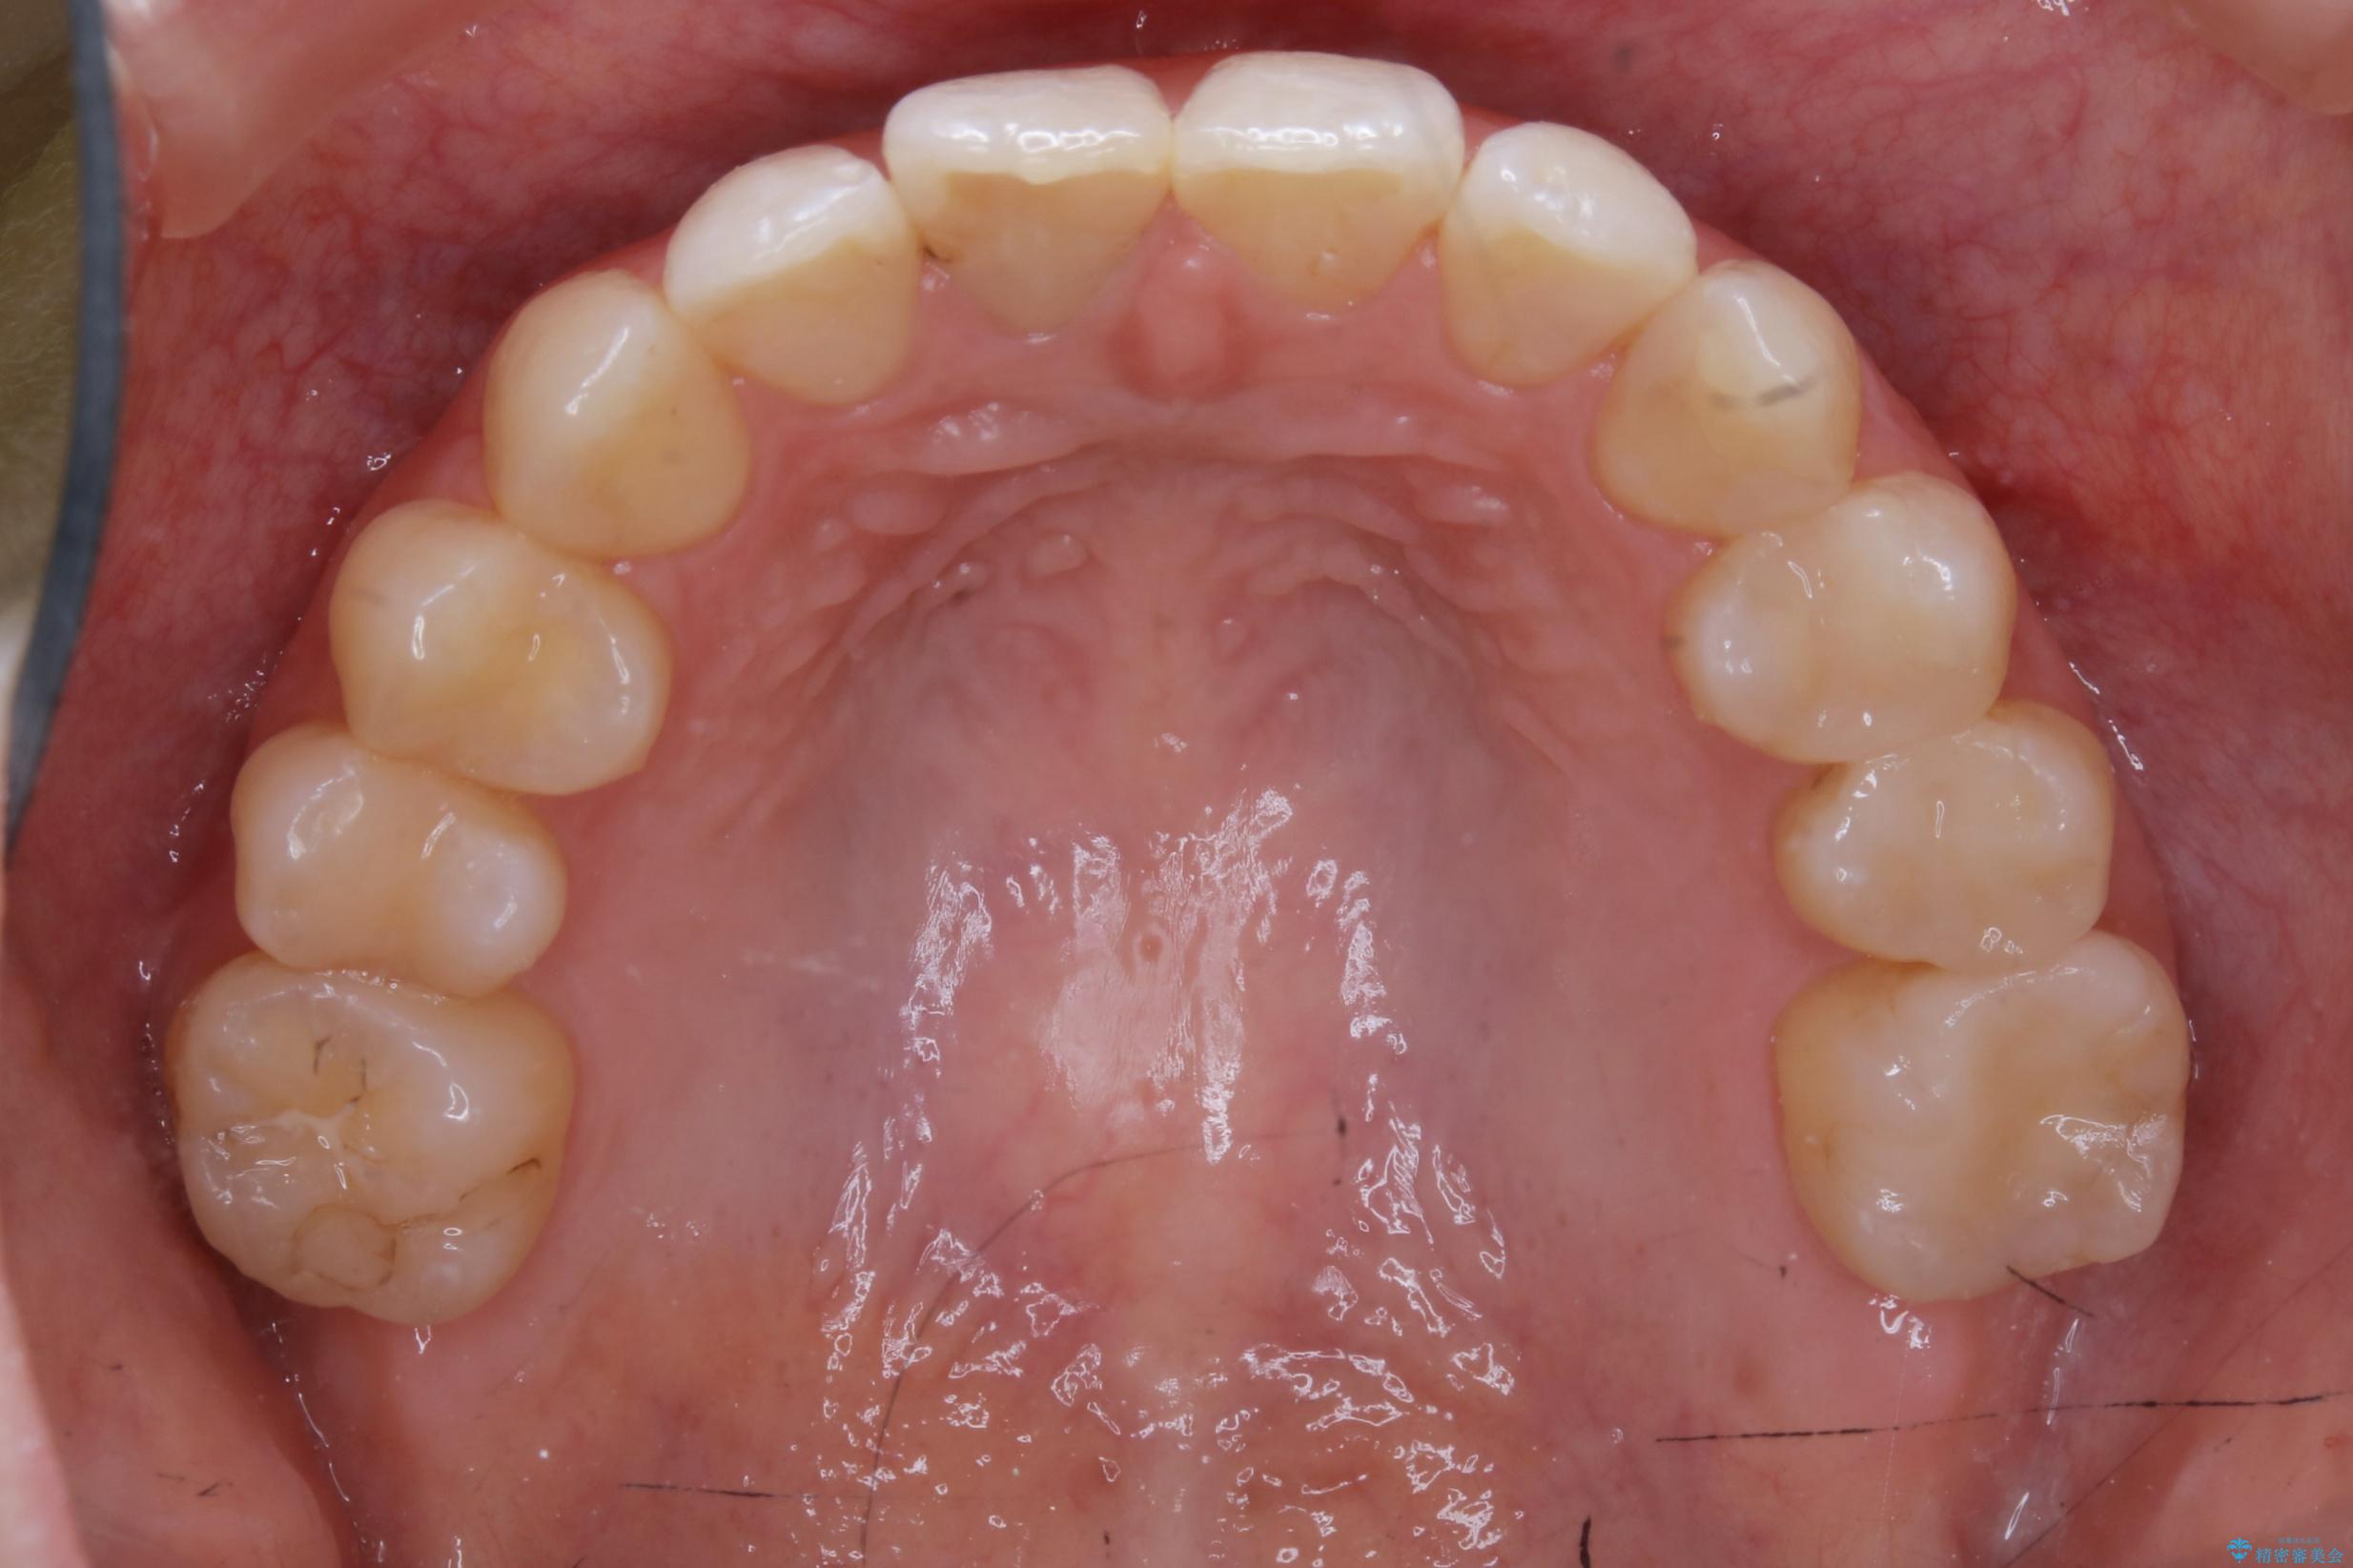

治療後

20代 女性 非抜歯で歯列をコンパクトに20代 女性 非抜歯で歯列をコンパクトに20代 女性 非抜歯で歯列をコンパクトに